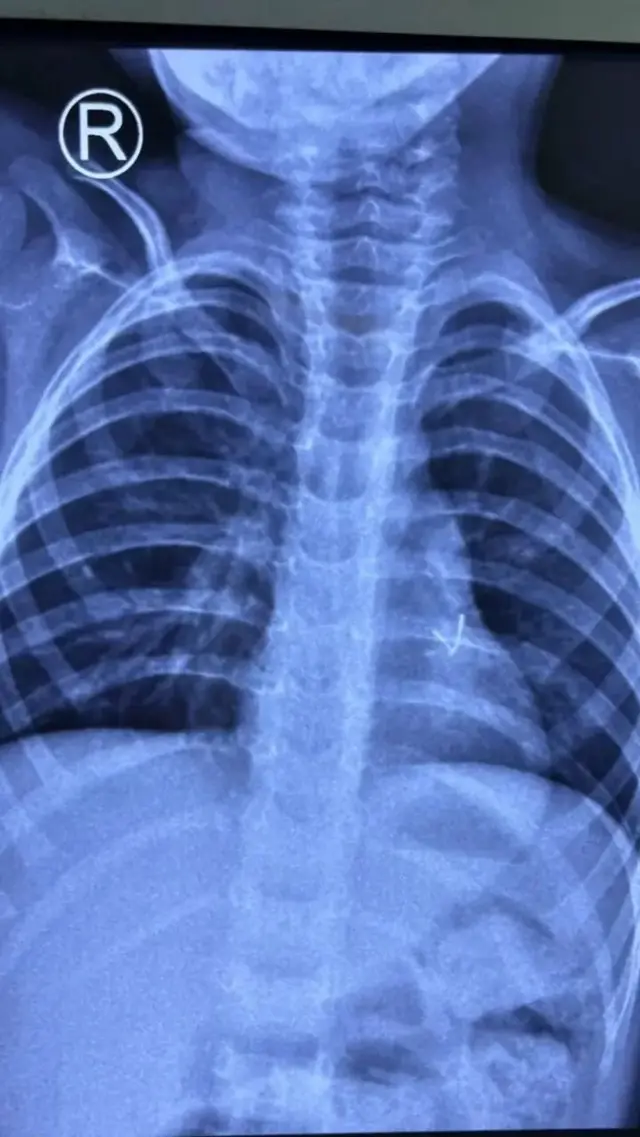

"Haddii wax noocaas ah ku dhaco dhuunta ilmaha, ilmuhu wuu ooyi doonaa kadibna muddo ka dib wuu dagi doonaa. Markaas waa in aad u tagtaa takhtarka si loo sameeyo sawir raajo ah oo laabta iyo caloosha ah, iyadoo loo raacayo talooyinkooda daaweynta."

Dhakhaatiirtu waxay sameeyaan sawirro raajo ah oo laabta iyo caloosha ah si ay u ogaadaan meesha walaxdu ku sugan tahay iyo sida loo saaro.